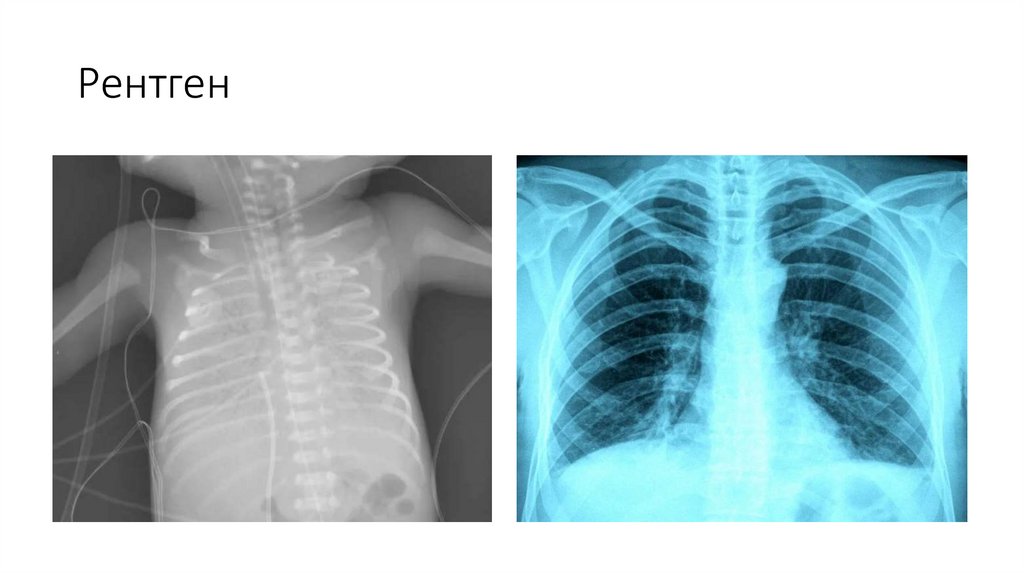

Рентген